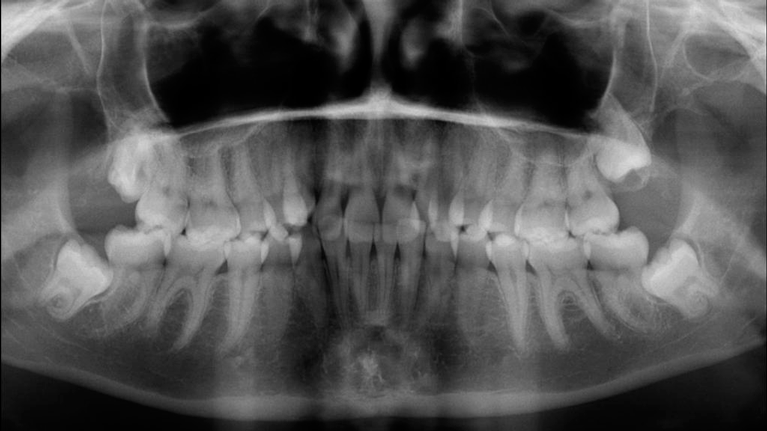

Til konferencen møder du en kirurgisk specialtandlæge fra Kæbekirurgisk Afdeling, muligvis en uddannelsestandlæge og en bøjletandlæge. De fremlægger den foreløbige behandlingsplan, som de forinden har udarbejdet. Du har mulighed for at få uddybet eventuelle spørgsmål til behandlingsplanen.

Du skal være færdigudvokset før operationen. Dette undersøger vi vha. et røntgenbillede af din hånd. Du får taget røntgenbilledet enten hos bøjletandlægen eller på Kæbekirurgisk Ambulatorium.